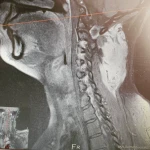

Es geht um einen Tumor in der HWS. Nicht Operabel - 50 Chemos als auch Bestrahlungstherapien haben nicht angeschlagen. Der Tumor wächst weiter, in der Kopf.

Anna leidet unter Starken Schmerzen im Linken Arm, nach langen Besuchen bei verschiedenen Ärzten kommt nach 11 Monaten die Schock Diagnose! Ein Tumor in der HWS Verwachsen. Direkt ging es nach Hannover - Biopsien entnehmen - Ärzte Besprechung - Alarm - Diese Art Tumor ist noch nicht bekannt, was aber klar ist, er wächst unfassbar schnell und ist sehr Bösartig.

50 Chemotherapien - Erfloglos! Der Tumor hat sich nicht verändert, ganz im Gegenteil, er wächst weiter.

Nach den Erfolglosen Chemos- Unzählige Bestrahlungstherapien. Nach den ersten Sitzung ein klitzekleiner funken Hoffnung. Sie konnten das Wachstum Kurzeitig einstellen - allerdings nicht lange. 5 Monate erfolg, danach ging es weiter. So lange bis die Therapien ausgeschöpft waren und der Körper Pause brauchte.